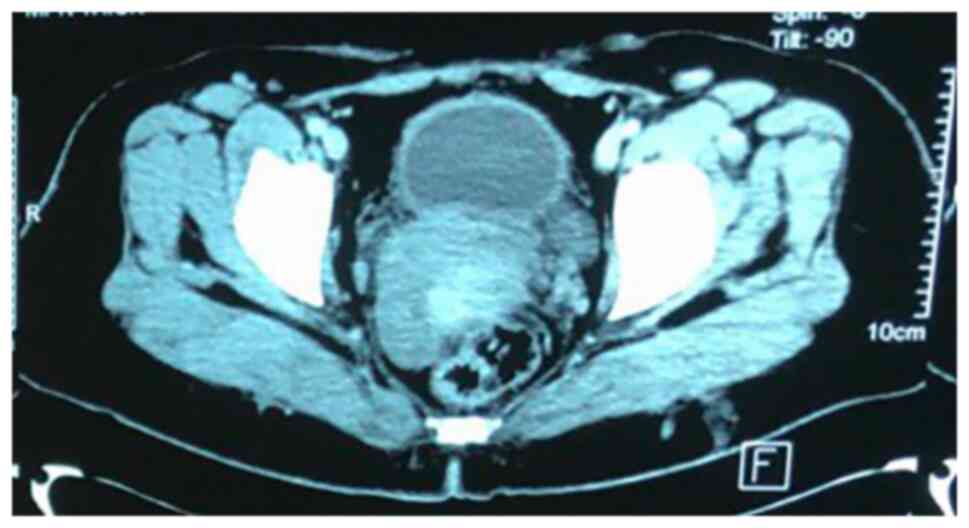

Initial diagnostic workup included an abdominal ultrasound (U/S), which was followed by a contrast-enhanced computed tomography (CT) scan as the previous surgery had been based on the U/S alone. The CT scan was performed to provide a more detailed assessment of the bladder wall and surrounding structures, which revealed irregular, thickened bladder walls (8 mm), but no gross mass lesion due to the previous TURBT procedure (Fig. 2). Given the history of adenocarcinoma and to assess potential metastasis, a fluorodeoxyglucose positron emission tomography (FDG-PET) was recommended by the multidisciplinary team. The FDG-PET was crucial for detecting any hypermetabolic nodular lesions suggestive of metastatic spread; however, the results revealed no abnormal focal hypermetabolic nodular lesions in the urinary bladder wall or elsewhere in the body (Fig. 3). Based on the PET scan findings and the initial TURBT biopsy, which revealed a T2-stage adenocarcinoma, a radical cystectomy was advised for definitive management.

Figure 2

A contrast-enhanced CT scan of the pelvis indicating a mildly thickened urinary bladder wall; however, no obvious mass is present, and the bladder appears small in size.